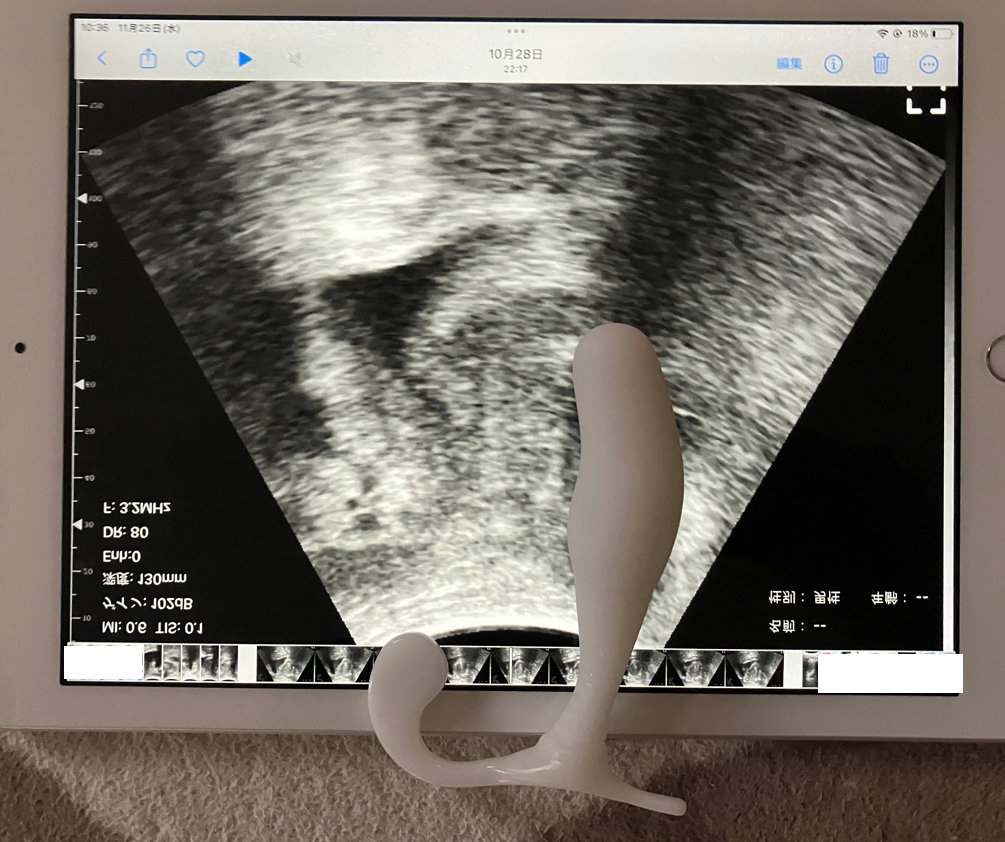

タブレットで実寸大で表示してEX2を置いてみた画像です。

ネット上の画像だと直腸のすぐ前に前立腺が描かれているものがありますが、

この画像を見るにわたしのは前立腺が一個分前寄りにあるので、ストレートな器具だと前立腺にあたらないようです。